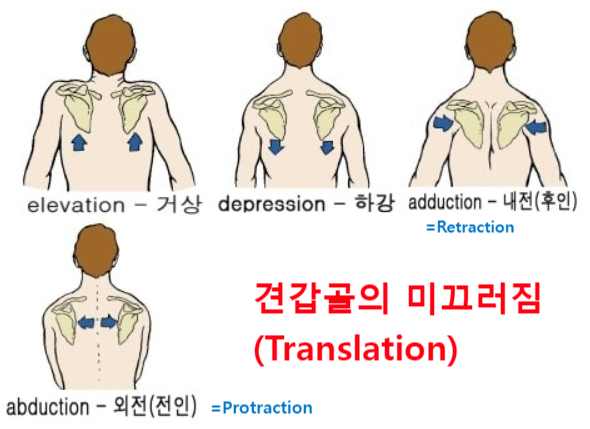

견갑골의 움직임은 3가지 움직임(Motion)과 2가지 미끄러짐(translations)으로 나눌 수 있습니다.

2. 미끄러짐(Translation) - 특정 평면을 따라 미끄러짐 운동

거상(Elevation) / 하강(Depression) = Upward/downward sliding on the thorax

내전(후인, Adduction) / 외전(전인, Abduction) = Medial/lateral sliding around the curvature of the thorax